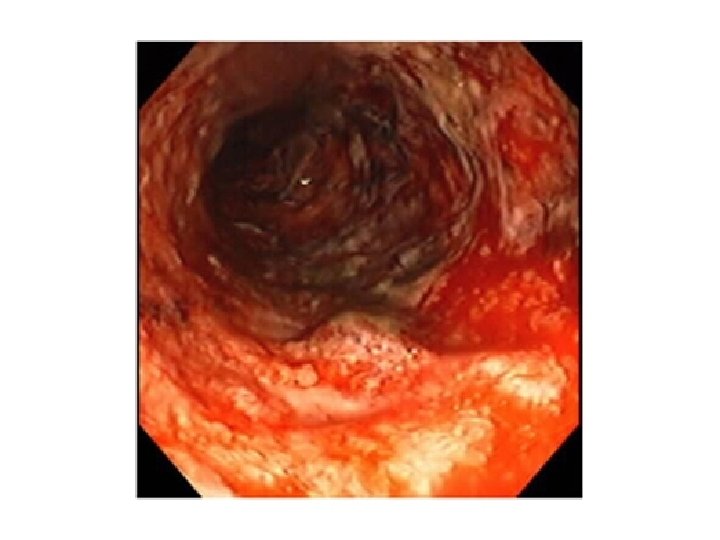

• Odnos inhibicije COX-1/COX-2 određuje verovatnost neželjenih dejstava. • COX-1 nastaje normalno u zdravoj ćeliji, gde prostaglandini imaju zaštitnu ulogu (produkcija želudačne sluzi i održavanje protoka krvi) • COX-2 inducibilni oblik enzima povezan sa zapaljenjem. Inhibicija COX-2 odgovorna za antizapaljenjsko delovanje NSAR, a inhibicija COX-1 za GI i bubrežna neželjena dejstva

• Najmanji rizik ima ibuprofen (1200 mg/dan), dok su indometacin i oksikami (piroksikam) lekovi sa visokim rizikom od GI i bubrežnih neželjenih dejstava. • Selektivni COX-2 inhibitori – koksibi imaju mali rizik kao ibuprofen, ali otkriće novih ozbiljnih neželjenih dejstava (povećanje učestanosti kardiovaskularnih i cerebrovaskularnih incidenata) dovelo do povlačenja određenih koksiba sa tržišta (rofekoksib) i promene uputstva za preostale koksibe.

Izbor: • paracetamol (maks. 4 g /dnevno) • ibuprofen (1200 mg /dnevno) – ako je značajna zapaljenjska komponenta • NSAR – najmanja delotvorna doza, što kraće • izbegavati primenu NSAR sa visokim rizikom od ozbiljnih GI i bubrežnih neželjenih dejstava (indometacin, piroksikam) • inhibitori protonske pumpe su najbolja prevencija GI neželjenih dejstava